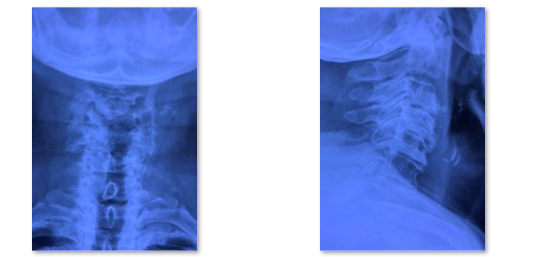

颈椎管狭窄症也是中老年人常见脊柱疾病,在椎管狭窄症发病率中仅次于腰椎管狭窄症。颈椎管狭窄症:构成颈椎管各解剖结构因发育性或退变因素造成骨性或纤维性退变引起一个或多个节段官腔狭窄导致脊髓血液循环障、脊髓及神经根压迫症者为颈椎管狭窄症。主要症状为1.感觉障碍:四肢麻木、过敏或疼痛,胸腹骨盆区发紧(束带感),严重者可有呼吸困难;2.运动障碍:四肢无力、僵硬不灵活,多数有下肢无力沉重、脚落地似踩棉花感,站立不稳,加重可出现四肢瘫痪;3.大小便障碍。颈椎管狭窄症患者CT或MRI通常表现为多节段颈椎间盘突出、黄韧带增生肥厚,颈椎椎管容积大大减小,脊髓多节段受压。

术前